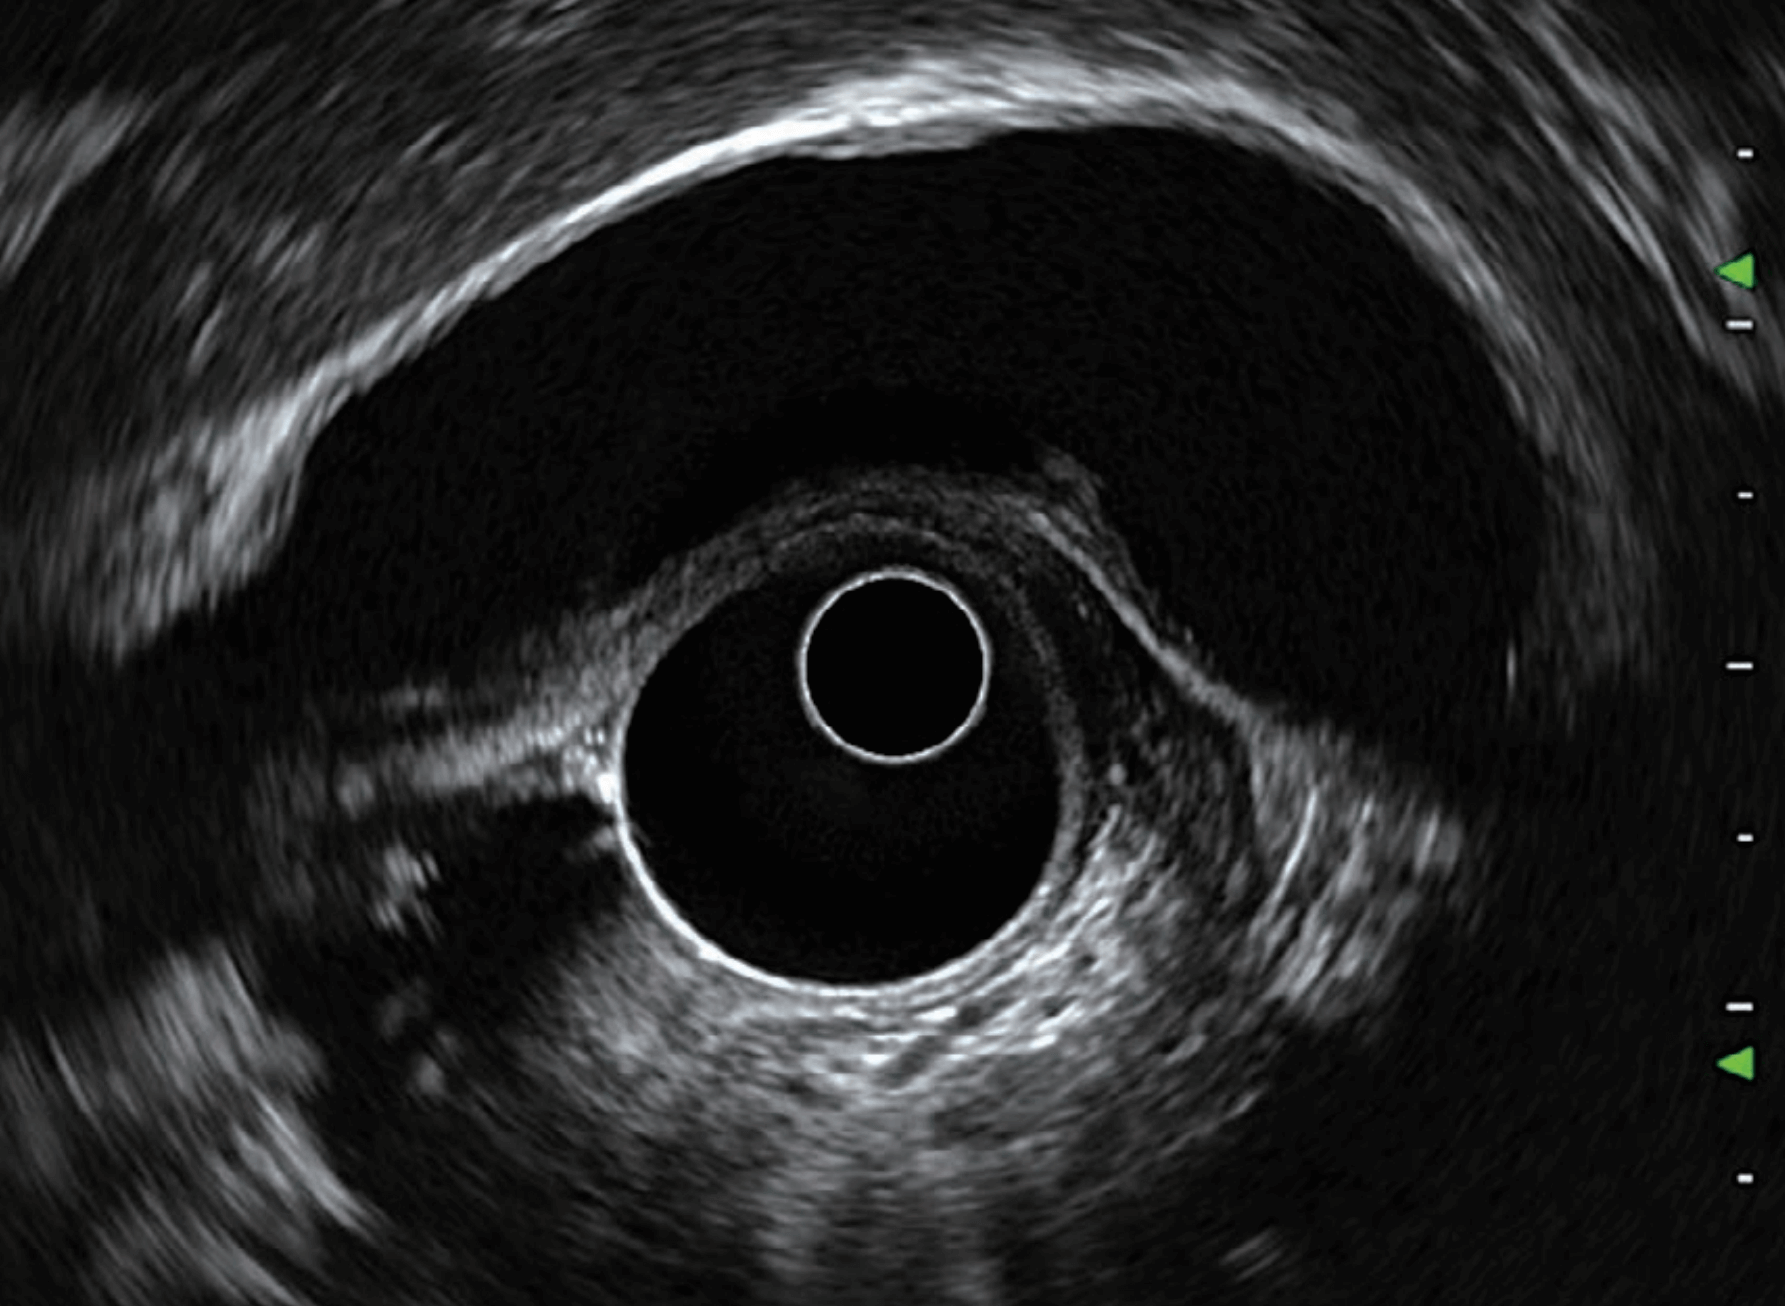

With artifacts (B-mode, at pancreatobiliary area)

With less artifacts (THE mode at pancreatobiliary area)

THE would be helpful to observe a target tissue by reducing the amount of artifacts in the image. THE image is developed by transmitting and receiving signals at different ultrasound frequencies. For example, in THE mode, the EUS scope would transmit ultrasound wave at a certain frequency, but it would be received at a higher frequency. This improves the image quality because body tissue reflects ultrasound waves at a higher frequency than that of what it was initially sent at. This results in clearer images that displays body tissue with less artifacts.